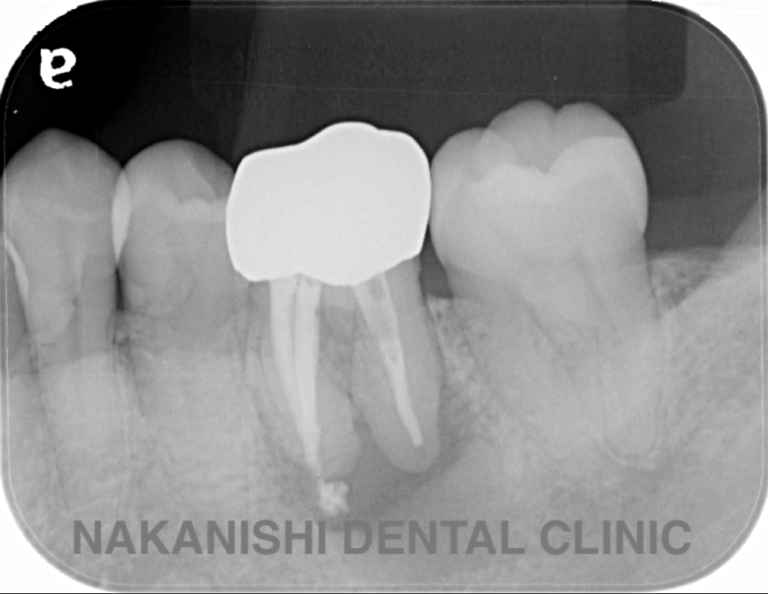

case 1.

治療前

治療後

| 主訴 | 右下歯ぐきの腫れ。 他院で抜歯と言われ、セカンドオピニオン希望でご来院。 |

|---|---|

| 治療期間 | 1か月 |

| 治療費 | 約2万円 |

| 治療内容 | ラバーダム、マイクロスコープ下にて根管治療を施術。歯肉腫脹と疼痛は消失し補綴物を作製し治療終了。治療後のレントゲン写真は2年後のものです。 |

| 治療のリスク | マイクロスコープやCTを使用し、可能な限り精密な根管治療を行っていますが、歯根の形態や病変の大きさ、過去の治療履歴などにより、治癒が得られない場合があります。 また、治療後に再感染や歯根破折が生じることもあり、その場合は再治療や抜歯が必要となることがあります。 治療結果には個人差があり、すべての症例で同様の経過を保証するものではありません。 |